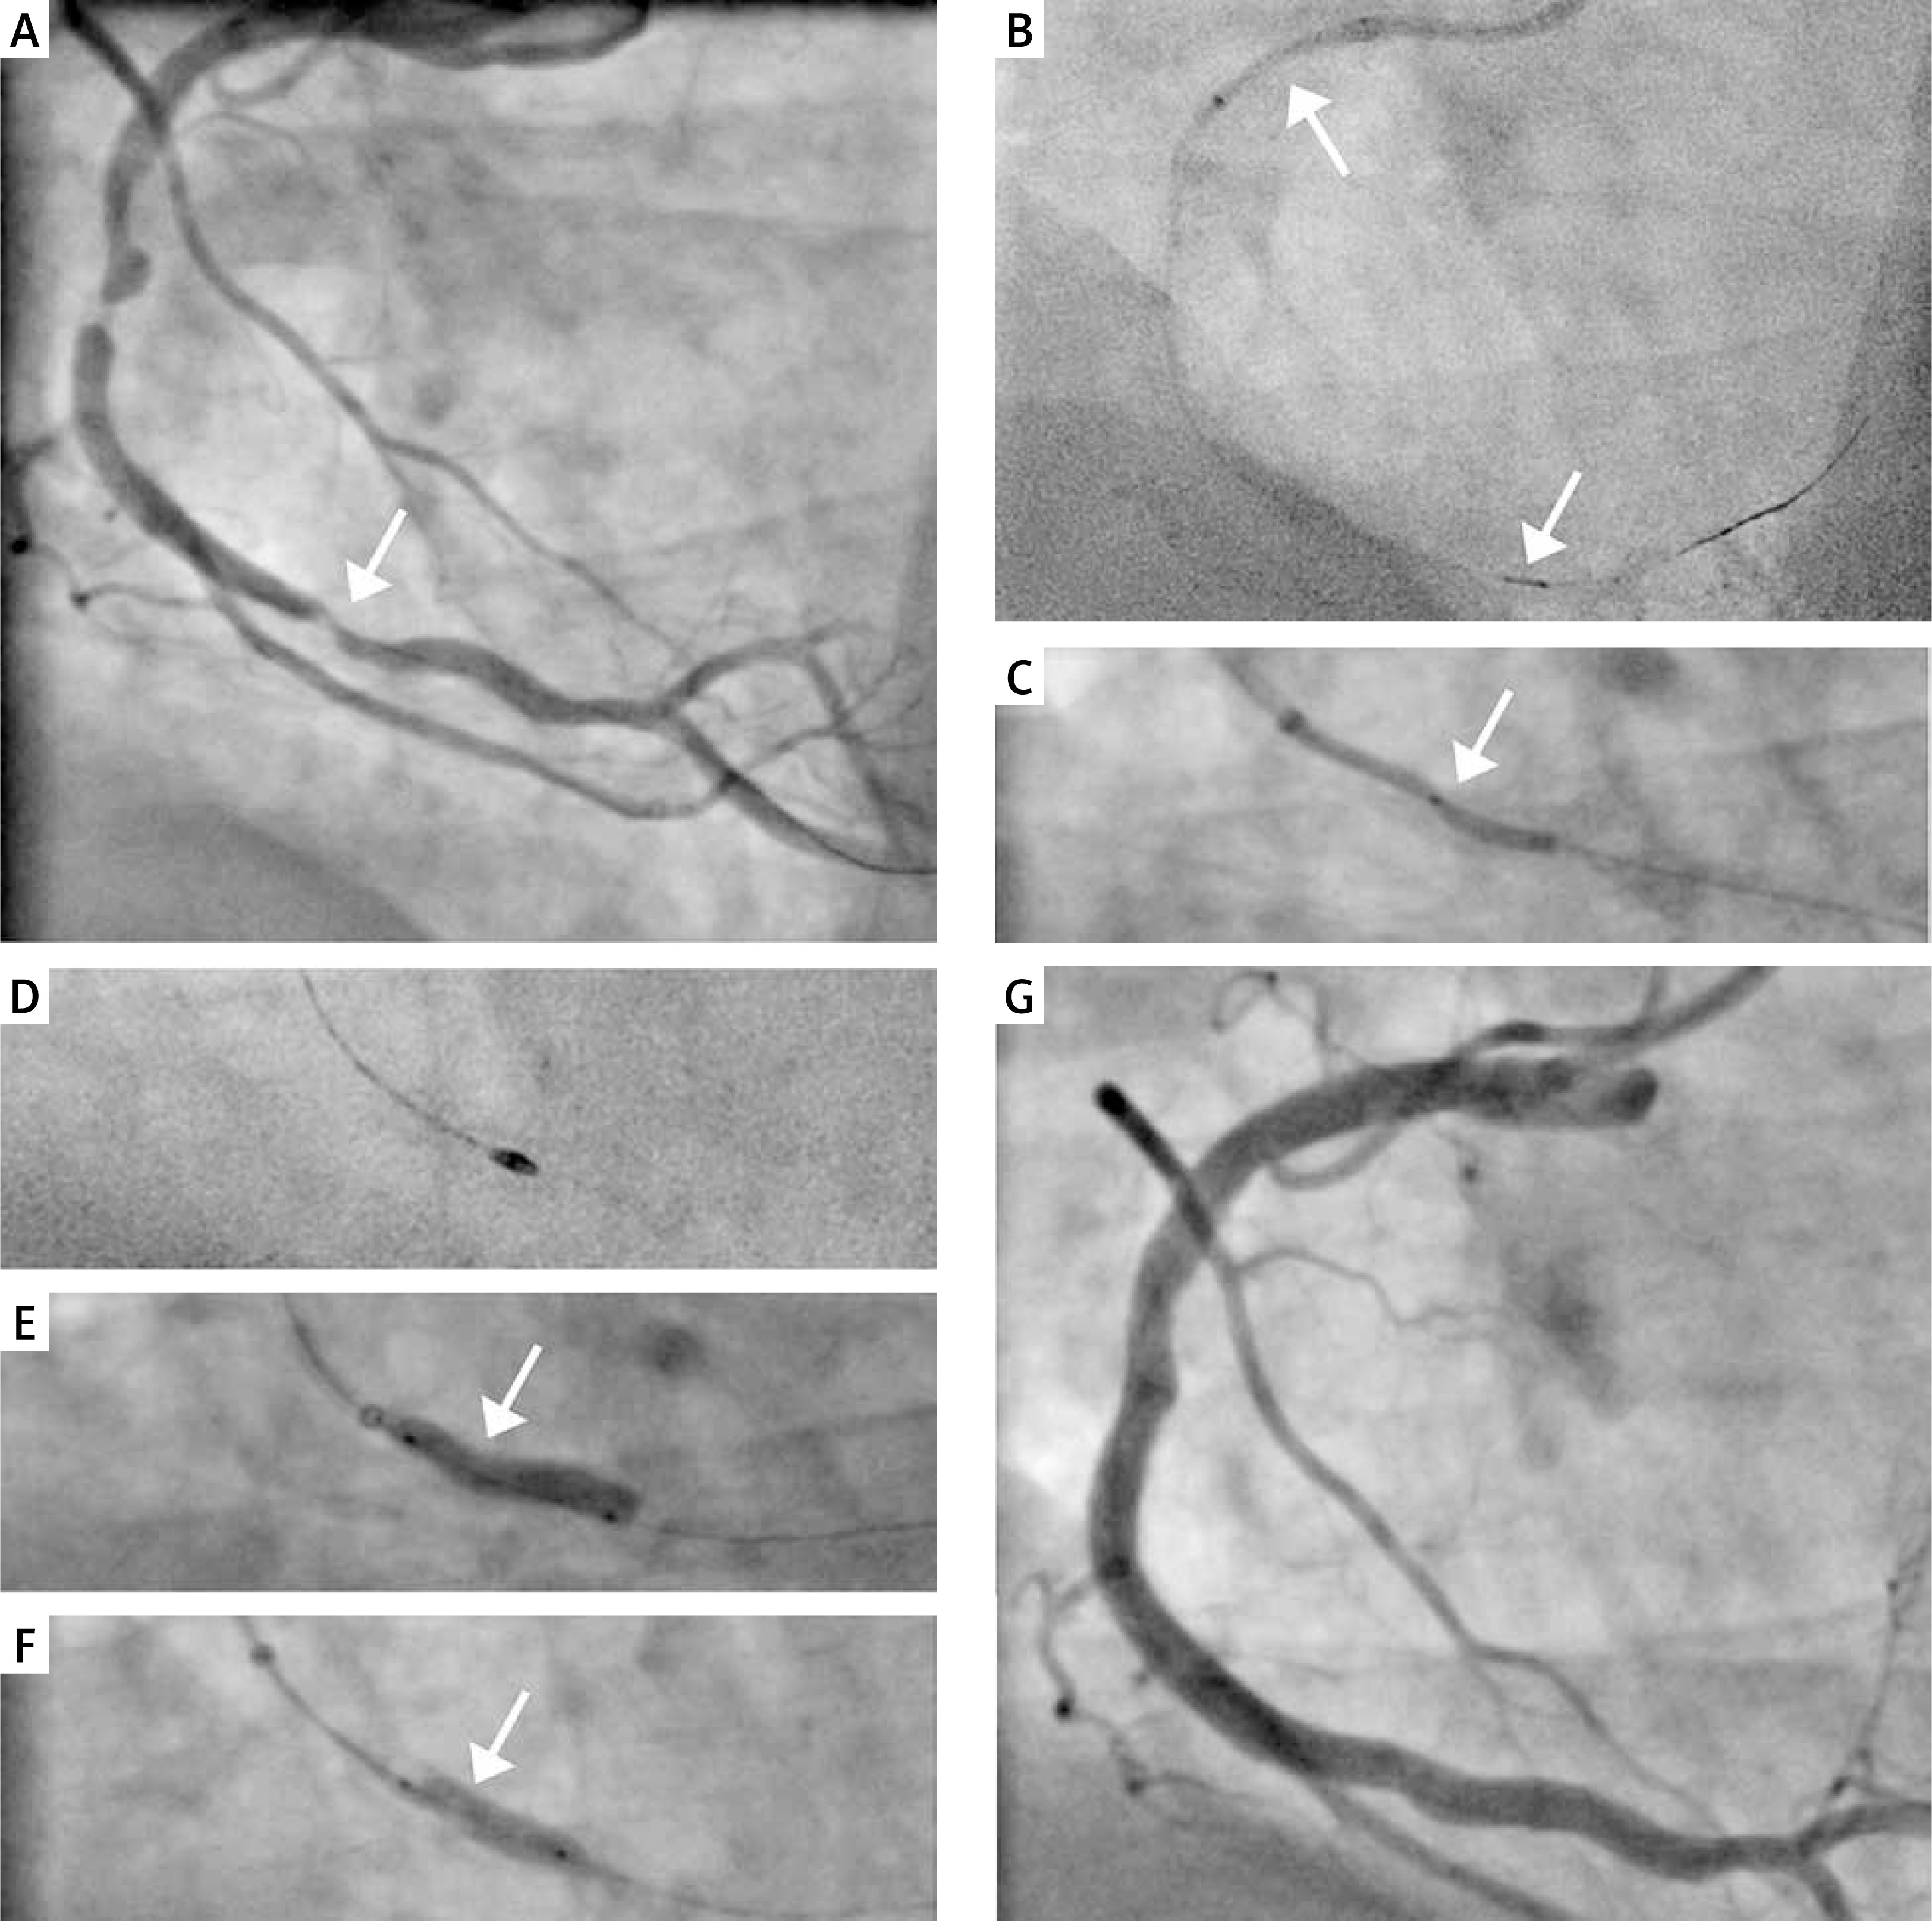

He was admitted to hospital with chest pain (class IV in the CCS scale) ongoing for 2 h. An electrocardiogram showed sinus rhythm 80/min conducted with the right bundle branch block (RBBB) and the serum high-sensitivity troponin-I was positive. Coronary angiogram revealed: chronic total occlusion of the LAD with two coexisting culprit lesions in the RCA (proximal in-stent restenosis and distal highly calcified subtotal lesion) (Figure 1 A). Accumulated Syntax Score was 39.5 points. Due to advanced atherosclerosis, comorbidities and ongoing ischemic symptoms a rescue PCI was performed by the right femoral approach using the AL 1.0 Guide-Catheter (7F) (Medtronic Ireland, Galway, Ireland). We managed to cross the distal lesion with a Choice ES guidewire (Boston Scientific, Marlborough, United States). Despite use of the 7F guiding extension TrapLiner (Teleflex Incorporated, Wayne, United States) all attempts to cross the lesion with the FineCross microcatheter (Terumo Corporation, Tokyo, Japan) and a low-profile balloon Ryurei 1.0 × 10 mm (Terumo) failed. The successful crossing was achieved using an additional support by TrapLiner (Teleflex) and Turnpike Gold 135 (Vascular Solutions LLC, Minneapolis, United States) (Figure 1 B) – a microcatheter with a threaded tip, providing rotational advancement when rotated clockwise. In the next step we performed ineffective predilation with Ryurei (Terumo) 1.5 × 20 mm. Significant underexpansion of the balloon catheter at 18 atm was observed (Figure 1 C). Therefore, we exchanged the guidewire on the Rotawire-Extra-Support (Boston Scientific) and performed successful rotational atherectomy (RA) with the ROTAPRO Rotational Atherectomy System (Boston Scientific) using a Rotablator burr size of 1.75 mm (Figure 1 D). Despite lesion preparation with the RA, we still observed a significant “dogbone effect” on the non-compliant (NC) Emerge (Boston Scientific) balloon 3.0 × 15 mm (22 atm) (Figure 1 E). Hence, we performed the S-IVL using a 3.5 × 12 mm catheter. Delivery of the device was facilitated by use of a guiding extension. After application of 40 ultrasonic pulses, full expansion was obtained (Figure 1 F). Implantation of three overlapping drug eluting stents – Resolute ONYX (Medtronic) 3.5 × 38 mm, 4.0 × 38 mm and 4.0 × 34 mm (16 atm) – was followed by a 4.0 × 20 mm (22 atm) NC Emerge (Boston Scientific) postdilation. Finally, we obtained a satisfactory angiographic result (Figure 1 G). On the 7th day after the procedure, the patient was discharged. Follow-up transthoracic echocardiography showed an enlarged hypokinetic left ventricle with coexisting thinning and lack of vitality related to the anterior wall, interventricular septum and apex (LVEDd/LVESd = 64 mm/50 mm) with reduced ejection fraction (EF~30%) and coexisting moderate functional mitral regurgitation, without other mechanical complications. Due to the previously observed analogical impairment of myocardial contractility, ICD implantation was scheduled.

Figure 1

A – Coronary angiography of the right coronary artery – two culprit lesions, B – successful lesion crossing with TrapLiner and Turnpike, C – underexpansion of 1.5 × 20 mm balloon catheter, D – rotational atherectomy with 1.75 mm burr, E – underexpansion of 3.0 × 15 mm non-compliant balloon catheter, F – full expansion of intravascular lithotripsy 3.5 × 12 mm catheter, G – final angiographic result